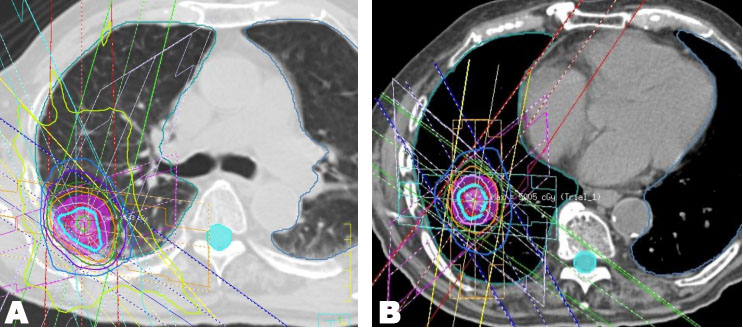

An 89-year-old man was diagnosed with stage I (T1cN0M0) adenocarcinoma in right lower lobe (Figure 4A). He had no previous history of smoking and an unremarkable medical history. He received initial SBRT at an irradiation dose of 48 Gy in 4 fractions at the isocenter (Figure 5A). The maximal PTV dose was 48 Gy. The MLD was 3.6 Gy, lung V5 was 23%, and lung V20 was 3.0%. Follow-up examinations were conducted 1, 3, 6, 9, and 12 months after initial SBRT in the first year, and then every three months. Although the lung tumor shrank, three years and six months after initial SBRT, a new lesion, distant form the lung tumor, has developed in the same lobe (right lower lobe). Serial enlargement and increased uptake on FDG-PET/CT were evident (Figure 4B and Figure 4C), which led to a diagnosis of lung metastasis or new primary lung cancer without pathological proof and, thus, the patient received repeat SBRT. The repeat SBRT irradiation dose was 50 Gy in 4 fractions (Figure 5B). The maximal PTV dose was 50 Gy. The MLD was 3.1 Gy, lung V5 was 18%, and lung V20 was 4.0%.

Figure 5: (A) Initial SBRT irradiation dose of 48 Gy in 4 fractions. (B) Repeat SBRT irradiation dose as a salvage option for local recurrence of 50 Gy in 4 fractions.